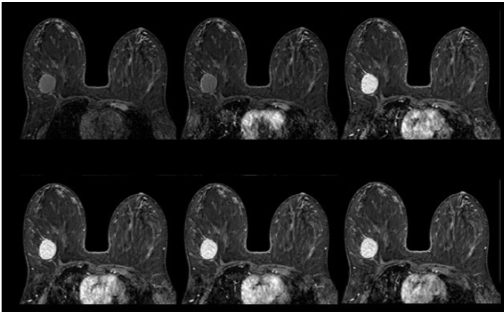

乳腺MRI : Breast MRI

造影剤を使った乳腺の検査です

乳腺MRIの検査は造影剤を使用し、うつ伏せで行う検査です。

乳がんの検出感度が高く、マンモグラフィのような圧迫による痛みはありません。遺伝的に乳がんに罹りやすい方に有効的な検査です。